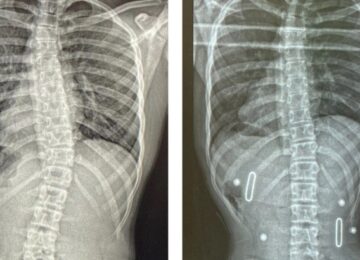

نوفمبر 9, 2025 قياس دوران الفقرات مع اعوجاج العمود الفقري: كيف يحددها الطبيب؟… scoliosis, اعوجاج العمود الفقري, الجنف لا يوجد تعليق 113 المشاهدات قياس دوران الفقرات مع اعوجاج العمود الفقري: كيف يحددها الطبيب؟ يُعتبر اعوجاج العمود الفقري (Scoliosis) من أكثر الاضطرابات شيوعًا بين الأطفال والمراهقين، ويتميز بانحناء جانبي للعمود الفقري مصحوب غالبًا بدرجة من الالتفاف أو الدوران